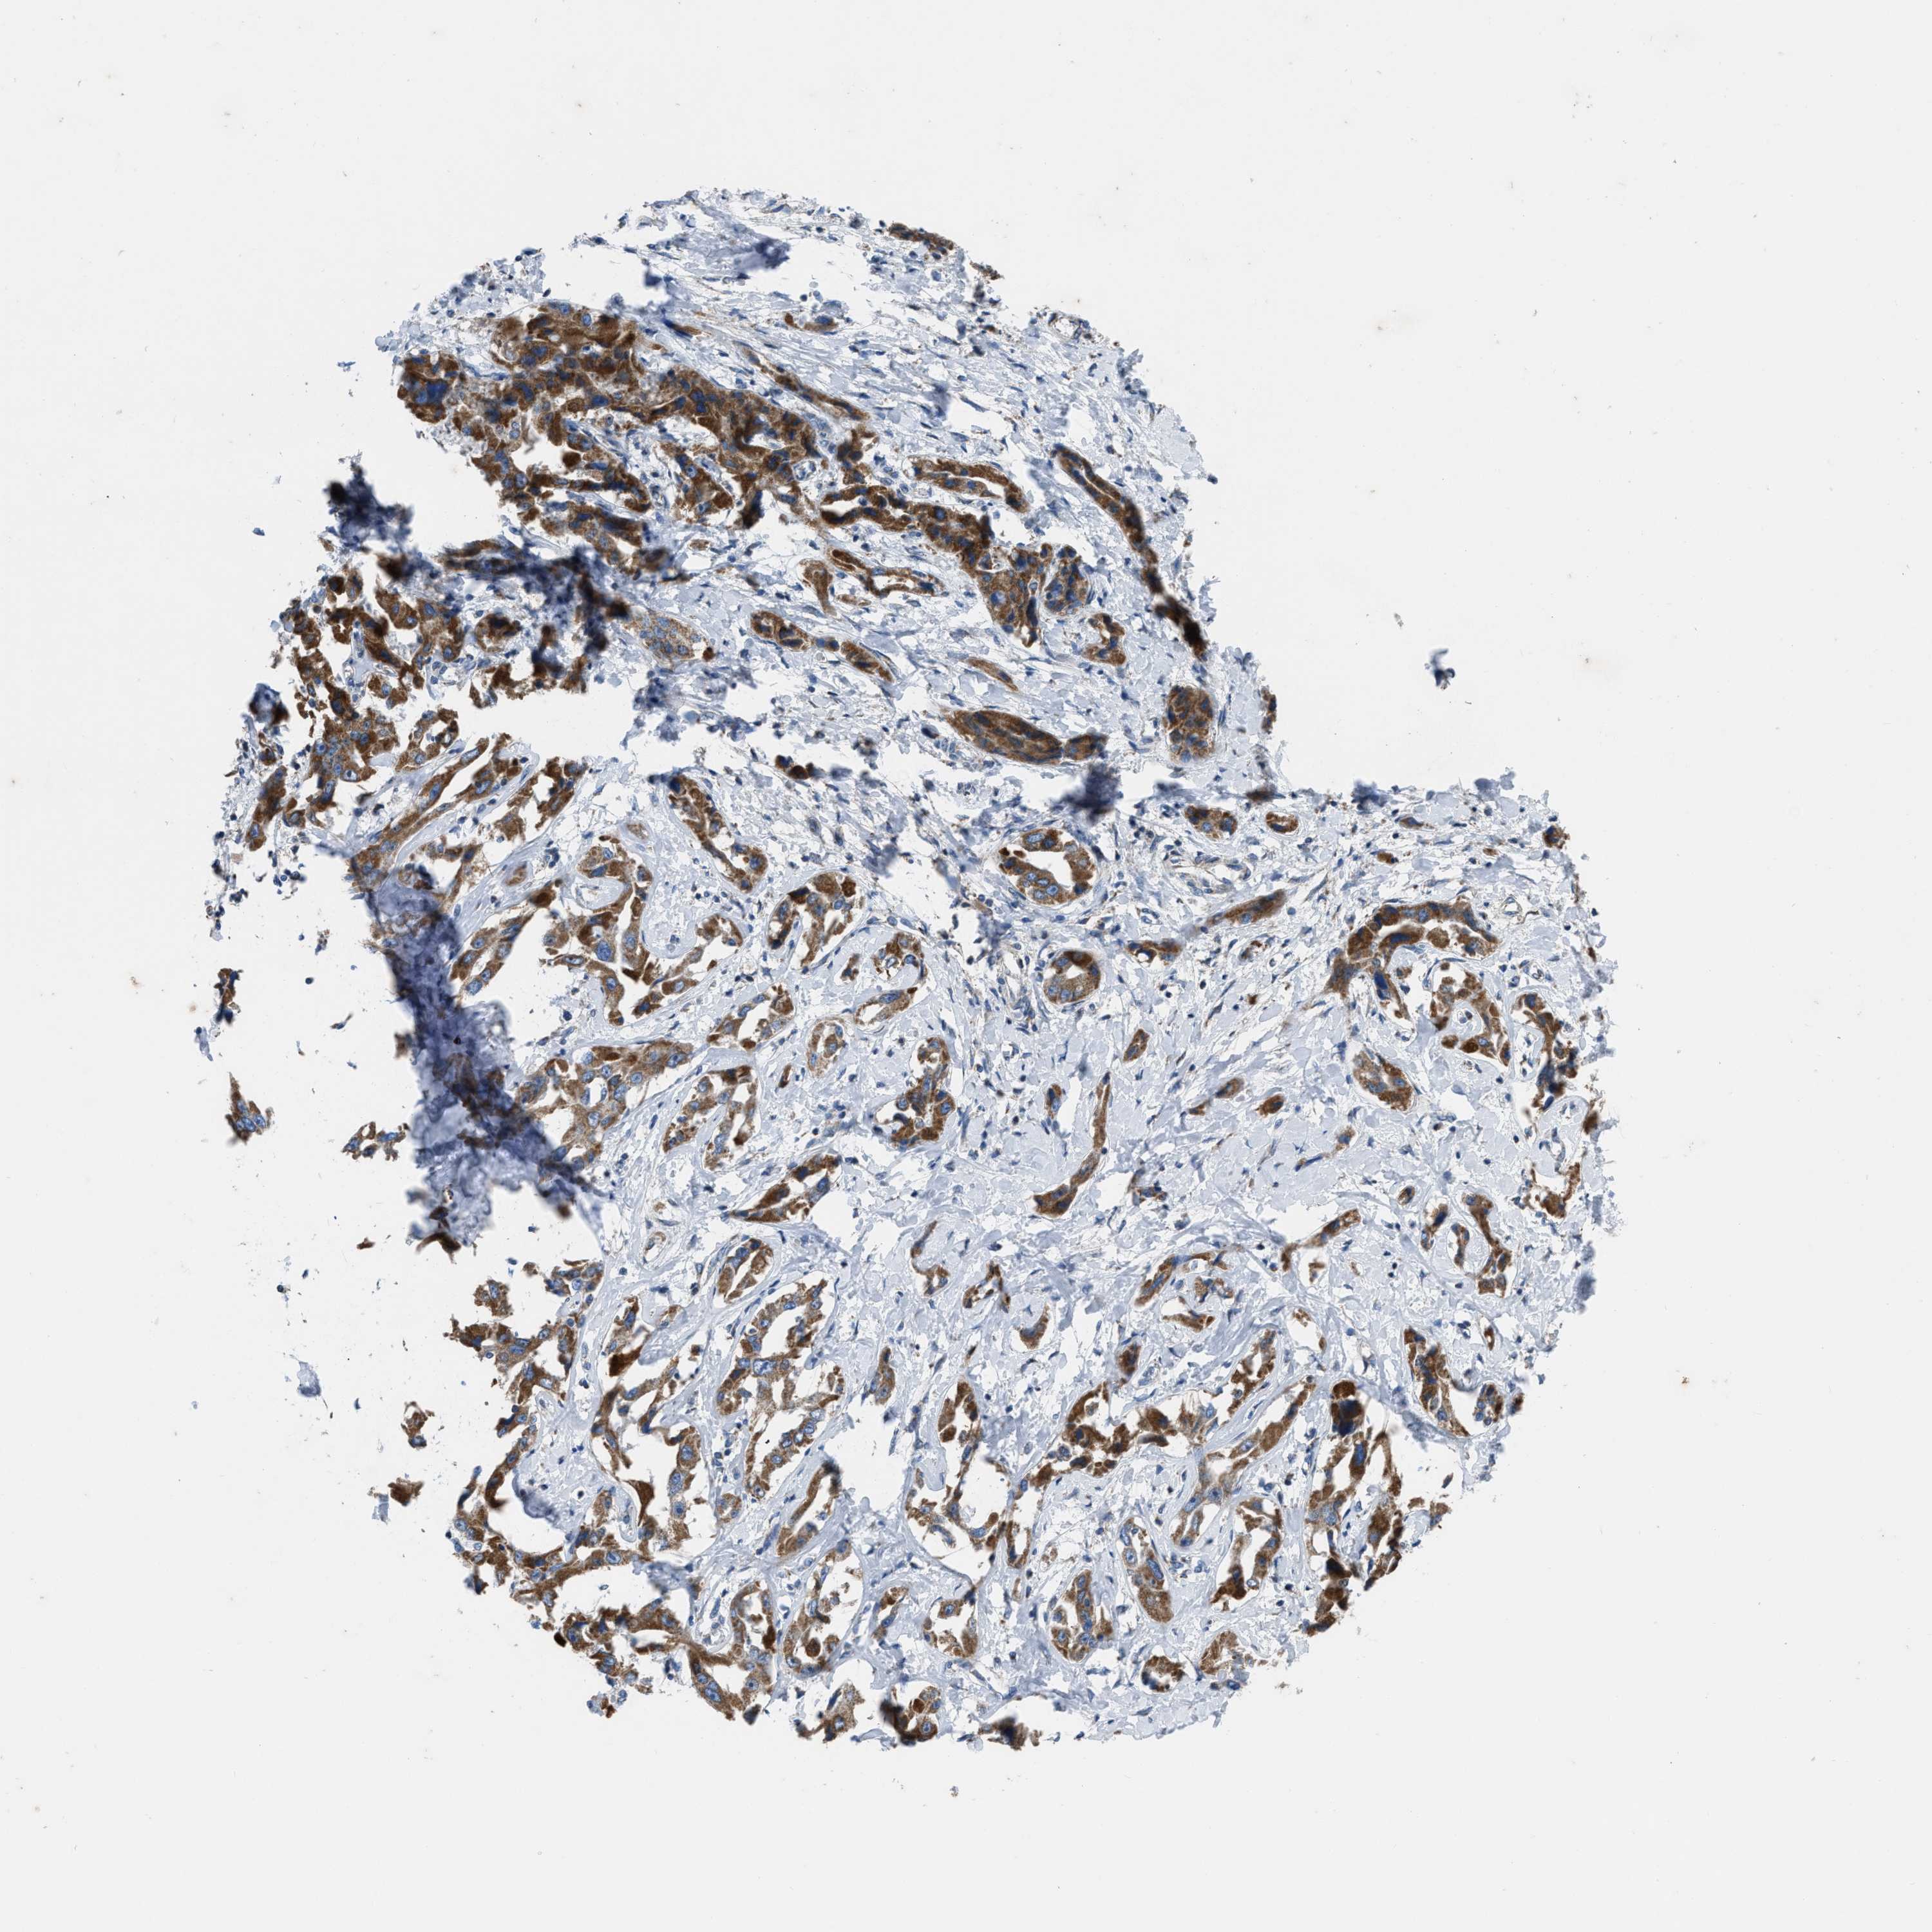

LIVER CANCER - Protein expressioni

A mouse-over function shows sample information and annotation data. Click on an image to view it in a full screen mode. Samples can be filtered based on level of antibody staining by selecting one or several of the following categories: high, medium, low and not detected. The assay and annotation is described here.

Note that samples used for immunohistochemistry by the Human Protein Atlas do not correspond to samples in the TCGA dataset.

Antibody stainingi

Antibody staining in the annotated cell types in the current human tissue is reported as not detected, low, medium, or high, based on conventional immunohistochemistry profiling in selected tissues. This score is based on the combination of the staining intensity and fraction of stained cells.

Each image is clickable and will lead to virtual microscopy that enables deeper exploration of all samples and also displays staining intensity scores, fraction scores and subcellular localization as well as patient and tissue information for each sample.

Antibody HPA018910

Antibody HPA018921

Antibody HPA018923

Staining

High

Medium

Low

Not detected

Intensity

Strong

Moderate

Weak

Negative

Quantity

>75%

75%-25%

<25%

None

Location

Nuclear

Cytoplasmic/membranous

Cytoplasmic/membranous,nuclear

Cholangiocarcinoma

Carcinoma, Hepatocellular, NOS